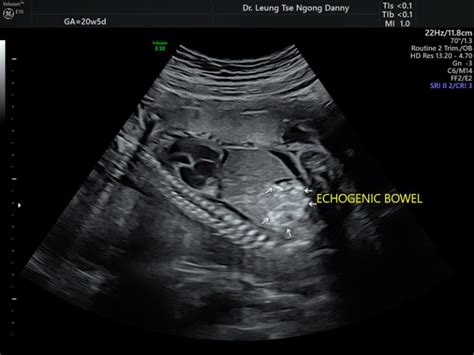

So, let’s dive right into understanding echogenic bowel , a term that often causes a little flutter of anxiety when it’s mentioned after a 20-week ultrasound. Simply put, when an ultrasound technologist or doctor says a baby has echogenic bowel , they’re referring to a specific appearance of the baby’s intestines on the ultrasound screen. “Echogenic” means it appears brighter, or whiter, than what’s typically expected for a fetal bowel. Think of it like this: on an ultrasound, different tissues reflect sound waves differently, creating varying shades of grey, black, and white. Bone, for instance, is very echogenic and appears bright white. Normally, a baby’s intestines during the 20-week anatomy scan should look similar in brightness to the liver, which is a medium grey. If the intestines appear as bright as, or even brighter than, the surrounding bone structure, then it’s classified as echogenic bowel . It’s a visual observation, not a direct diagnosis of a specific condition itself, but rather a marker that prompts further investigation. This particular finding occurs in about 0.2% to 1.8% of all pregnancies, which means while it’s not super common, it’s also not unheard of. The reason for this increased brightness can vary widely. Sometimes, it’s due to the presence of blood in the fetal gut, which could be from a small bleed. Other times, it might be due to a thicker-than-normal meconium (the baby’s first stool) because of a lack of fluid. Occasionally, it could signify some calcification or a slight increase in tissue density within the bowel. The key takeaway here is that echogenic bowel is a finding that needs context. It’s like a red flag that says, “Hey, let’s take a closer look,” rather than an immediate alarm bell. The excellent news is that in a significant number of cases, perhaps even the majority, an isolated finding of echogenic bowel, meaning there are no other unusual findings on the scan, resolves on its own or turns out to be entirely benign, with the baby being perfectly healthy at birth. This is why getting comprehensive information and follow-up care is absolutely paramount. Don’t jump to conclusions, guys; let the experts guide you through the next steps, which are designed to give you peace of mind and the best possible care for your little one.